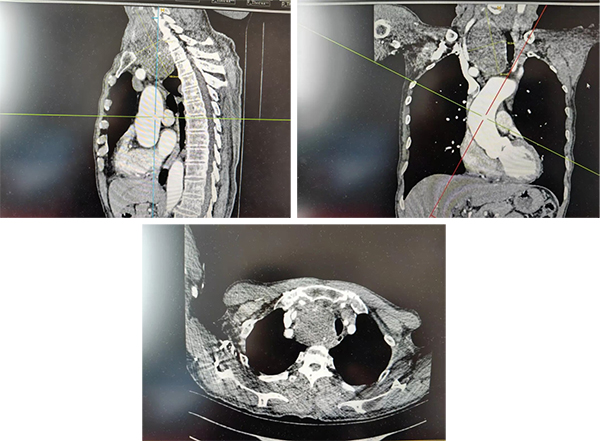

据悉,患者就诊时,甲状腺右侧叶已长出一枚巨大肿物。检查显示,该肿物最大直径约10cm,且大部分降入胸骨后,位置极深,解剖结构复杂给治疗带来极大挑战。更棘手的是,长期受巨大肿物压迫,患者气管严重左偏,呼吸功能明显受损;若不及时手术干预,肿物持续增大可能进一步压迫大血管、神经等重要组织,随时可能危及生命。然而,颈胸交接区域血管神经密集,胸膜顶结构复杂,加之肿物体积巨大、位置特殊,常规手术入路难以触及病灶,手术难度极高、风险极大,对手术团队的技术水平和协作度提出了严峻考验。

患者病情复杂,单一学科难以应对,必须集结多学科力量,制定最安全、最精准的诊疗方案。为确保手术万无一失,医院迅速启动多学科协作(MDT)诊疗模式,由心胸外科副主任段超普外科第二病区负责人李泽强麻醉科薛志强主任及手术室边旭护士长带领各自团队,开展术前多轮专题讨论。段超副主任作为心胸外科领域资深专家,擅长各类胸腔镜微创手术,在胸内复杂结构处理方面经验丰富;普外科第二病区负责人李泽强长期深耕普外科领域,在普外科疾病精准诊疗上造诣深厚;麻醉科主任薛志强团队针对患者气管严重左偏的特殊情况,反复评估麻醉风险、优化插管方案;边旭护士长团队则提前梳理手术流程,做好各项护理准备工作。多学科专家围绕患者病情、手术入路选择、麻醉方案优化、术中风险防控及术后护理干预等关键环节反复研判,最终确定采用“胸腔镜联合颈部手术入路”的微创方式,为患者量身定制个性化手术方案,既保证病灶完整切除,又最大限度降低手术创伤,保障手术安全。